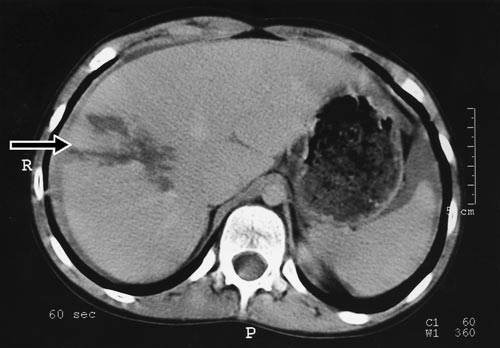

On examination, he was pale with a pulse of 130/minute and blood pressure of 100/60 mmHg. His abdomen was tender in the right upper quadrant with guarding. A CT scan of the abdomen revealed a large laceration to the right lobe of his liver, with a significant amount of free intraperitoneal fluid (Box 2).

The patient was observed closely in hospital for one week without adverse sequelae. Subsequent ultrasound scans showed resolution of his injury by four months.